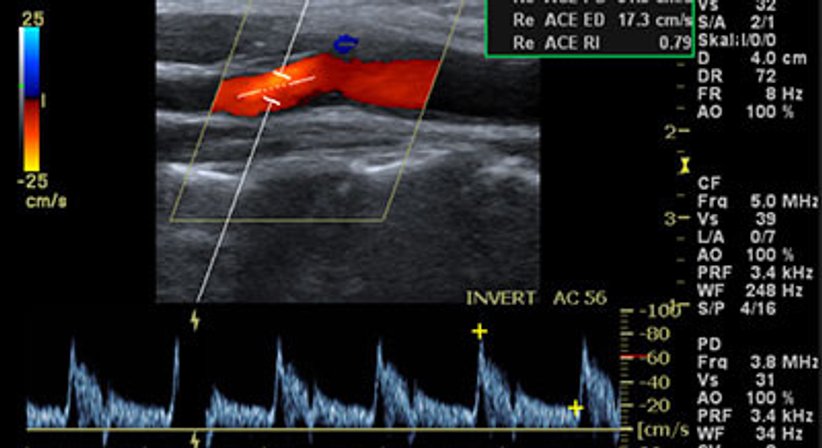

Mit dieser Untersuchung werden die Halsgefäße (Carotiden) mittels Ultraschall bildlich dargestellt. Dadurch können Ablagerungen (Plaques) oder Engstellen (Stenosen) frühzeitig erkannt werden, bevor es zu Durchblutungsstörungen oder Schlaganfall kommt.

Die Untersuchung ist schmerzfrei, ohne Strahlenbelastung und dauert nur wenige Minuten. Sie hilft, Ihr individuelles Risiko für Gefäßerkrankungen rechtzeitig einzuschätzen und gegebenenfalls vorbeugend zu handeln.